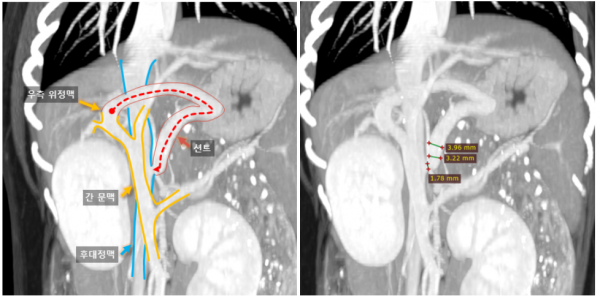

→ 영상진단에서는 소간증, 간외성 PSS 의심 소견이

나와 CT 진행 후 간문맥전신단락(PSS)를

진단하였습니다.

94e62ed5723a30503d8471b780ac418b_1759136028_0349.jpg

→ □□이에게 ameroid ring 결찰술과

간 생검을 진행했습니다.